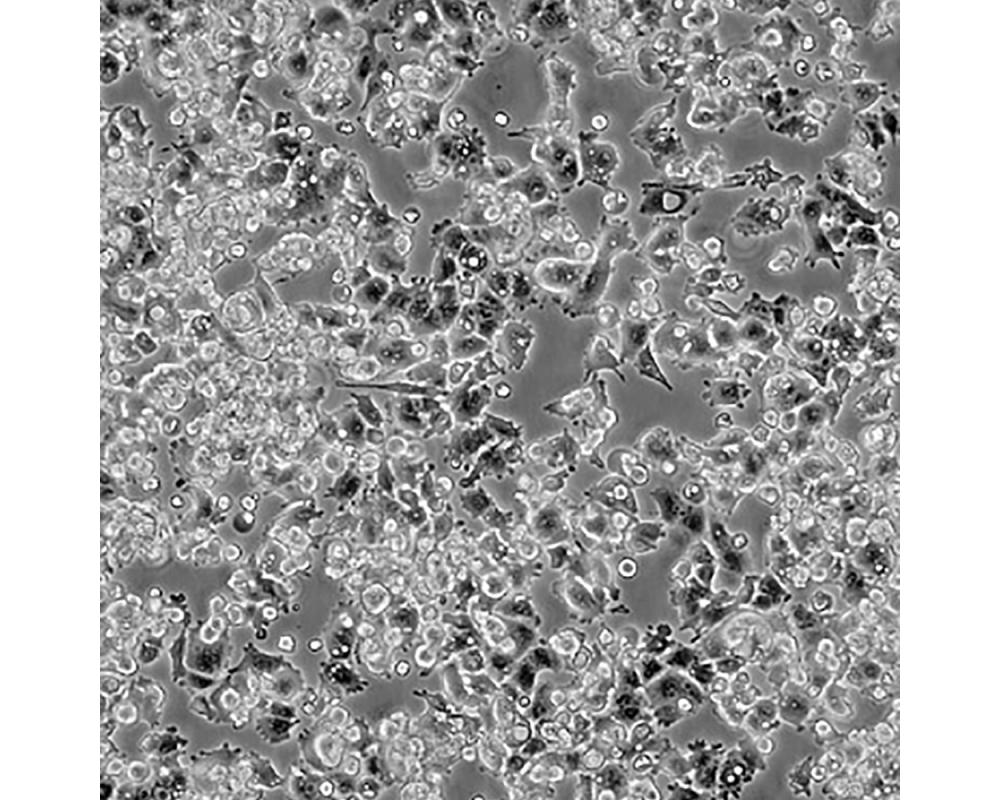

A-427

產(chǎn)品名稱 A-427

中文名稱 人肺腺癌細(xì)胞

組織來源 肺腺癌;男性

生長(zhǎng)特性 貼壁

細(xì)胞污染 HIV-1、 HBV、HCV、支原體、細(xì)菌、酵母和真菌檢測(cè)陰性。

培養(yǎng)基 1640,90%;FBS,10%;雙抗。

傳代方法 1:2-1:4

培養(yǎng)條件 Atmosphere: Air, 95%; CO2, 5%。Temperature: 37℃